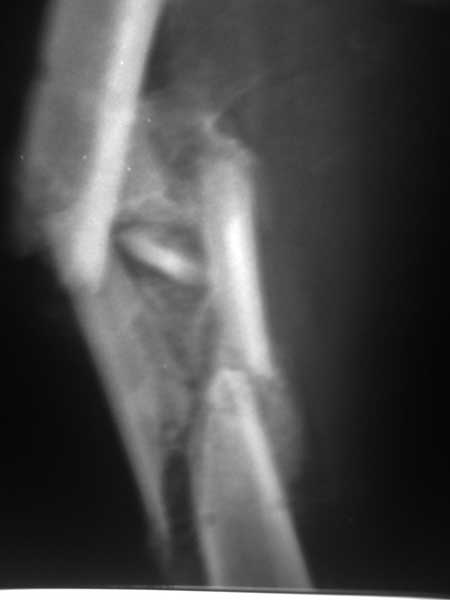

Пациент 39 лет. Травма в ДТП 2.5 месяца назад. Тяжелая сочетанная травма. ЗЧМТ. Тупая травма живота. Разрыв селезенки. Надрывы печени. Перелом бедра. При поступлении лапаротомия. Спленэктомия. Фиксация перелома бедра стержневым аппаратом. в последующем инфаркт мозга на фоне жировой эмболии. длительное нахождение на ИВЛ. Обширный пролежень в области крестца. и т.д.в настоящее время состояние больного стабилизировалось. активизирован на ходунках.имеется деформация бедра, укорочение 10 см. гранулирующий пролежень в области крестца. патологической подвижности в зоне перелома не отмечается.Оптимальные сроки проведения реконструктивной операции на бедре? Сейчас? Или после окончательного сращения?

А откуда такое укорочение взялось, 10см? По представленному фрагменту рентгенограммы понять трудно. В любом случае, если состояние пациента позволяет оперировать сейчас, зачем откладывать операцию до формирования монолитного сращения?

Конечно, снимки для планирования надо нормальные, не такой огрызок.

Спасибо за снимки. Предложения по тактике прежние.